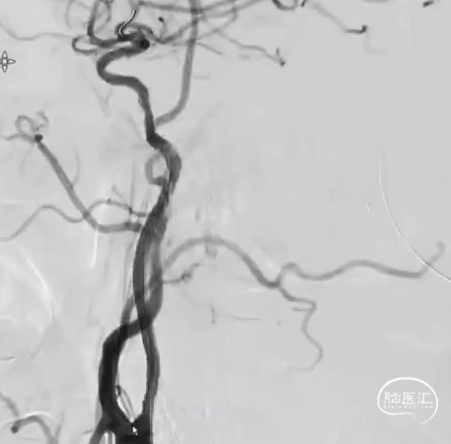

术前DSA R-CCA

术前DSA L-ICA

术前DSA L-VA

术前DSA R-VA

术后DSA R-CCA